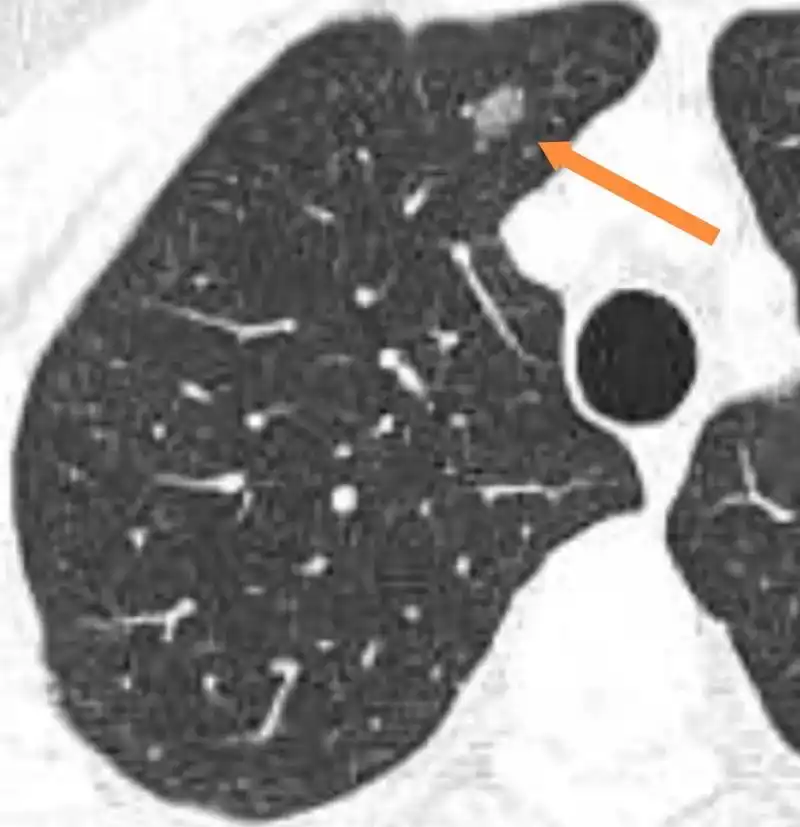

查体发现,病理结果为肺原位癌.手术后不需要化疗 - 抖音